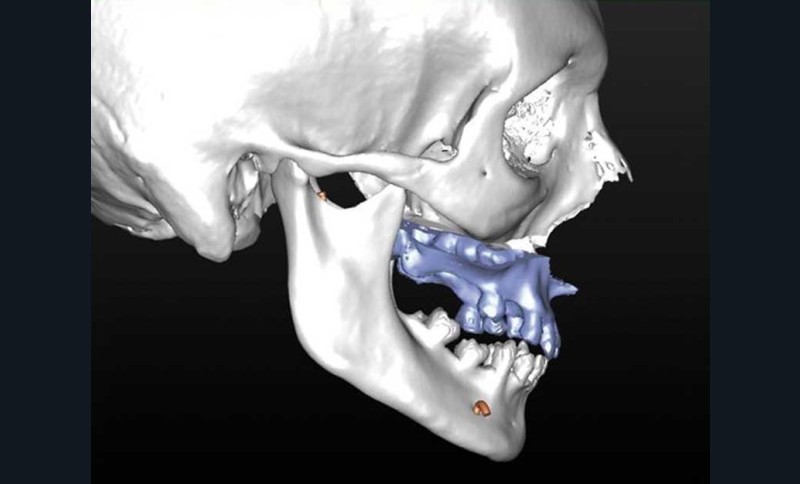

En cas d’hypo-divergence, qu’il s’agisse d’une classe II ou d’une classe III, la mandibule est stabilisée après avoir déterminé « l’espace libre d’innoclusion » (free way space) à l’aide d’une cale radio-opaque ou radio transparente (fig. 2 à 5).

– élaboration des images 3D en isolant des différents constituants anatomiques : crâne et maxillaire, mandibule, dents, dispositifs d’orthodontie, implants endo-osseux et prothèses conjointes éventuelles, etc.